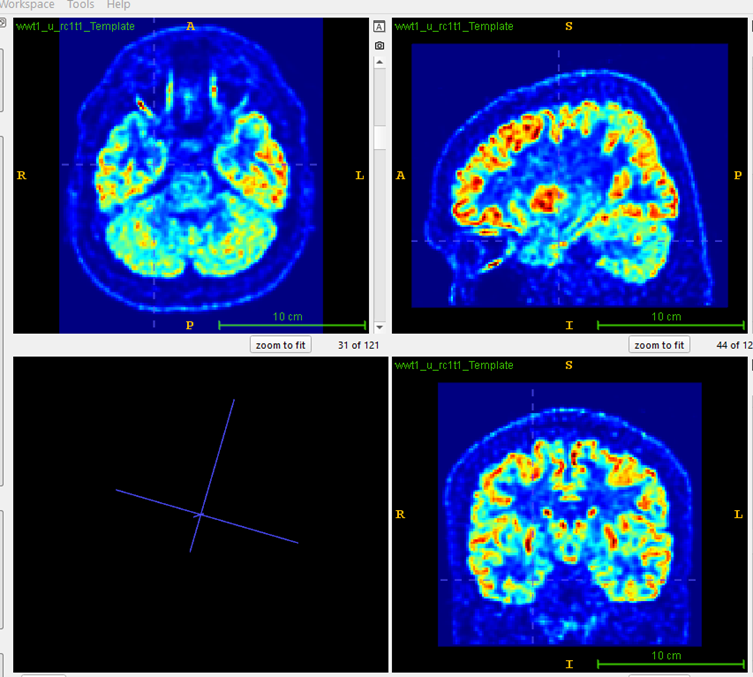

PASCOM: Focal hypometabolism was localized at the right inferior frontal lobe.

PASCOM: Focal hypometabolism was localized to right hippocampus and temporal pole cortex.

Clustered AI maps indicating focal hypometabolism

Overlay on native MRI for visual inspection